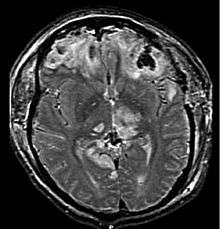

CT scan showing cerebral contusions, hemorrhage within the hemispheres, subdural hematoma on the left, and skull fractures[1] | |

Cerebral contusion, Latin contusio cerebri, a form of traumatic brain injury, is a bruise of the brain tissue.[2] Like bruises in other tissues, cerebral contusion can be associated with multiple microhemorrhages, small blood vessel leaks into brain tissue. Contusion occurs in 20–30% of severe head injuries.[3] A cerebral laceration is a similar injury except that, according to their respective definitions, the pia-arachnoid membranes are torn over the site of injury in laceration and are not torn in contusion.[4][5] The injury can cause a decline in mental function in the long term and in the emergency setting may result in brain herniation, a life-threatening condition in which parts of the brain are squeezed past parts of the skull.[3] Thus treatment aims to prevent dangerous rises in intracranial pressure, the pressure within the skull.

The distinction between contusion and intracerebral hemorrhage is blurry because both involve bleeding within the brain tissue; however, an arbitrary cutoff exists that the injury is a contusion if two thirds or less of the tissue involved is blood and a hemorrhage otherwise.[3]

Extensive contusion associated with subdural hematoma is called burst lobe.[5] Cases of a burst frontal or temporal lobe are associated with high mortality and morbidity.[5]

Numerous small contusions from broken capillaries that occur in grey matter under the cortex are called multiple petechial hemorrhages or multifocal hemorrhagic contusion.[14] Caused by shearing injuries at the time of impact, these contusions occur especially at the junction between grey and white matter and in the upper brain stem, basal ganglia, thalamus and areas near the third ventricle.[14] The hemorrhages can occur as the result of brain herniation, which can cause arteries to tear and bleed.[14] A type of diffuse brain injury, multiple petechial hemorrhages are not always visible using current imaging techniques like CT and MRI scans. This may be the case even if the injury is quite severe, though these may show up days after the injury.[15] Hemorrhages may be larger than in normal contusions if the injury is quite severe. This type of injury has a poor prognosis if the patient is comatose, even with no apparent causes for the coma.[15]